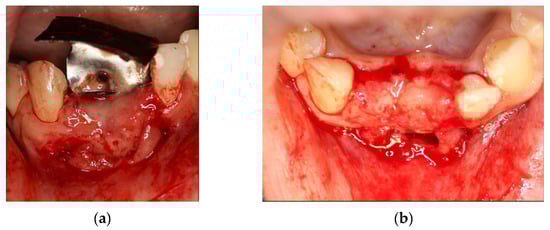

In this case, a cystic lesion involving three lower incisors was treated (Figure 13a).

Figure 13.

(a) Cystic lesion between lower incisors; (b) full-thickness flap, extraction of the three incisors and removal of the cyst.

Following a full-thickness flap, three incisors (4.2, 4.1 and 3.1) were extracted (Figure 13b). After a careful curettage of the cyst cavity, collagen sponges were grafted in the cavity. The collagen sponges were wet with surgical site blood (Figure 14a). A titanium foil (Figure 14b) was shaped and positioned and the flap sutured.

Figure 14.

(a) Extraction site filled with collagen sponges; (b) titanium foil and suture.

At the follow-up, a significant plaque accumulation on the foil surface was observed; nevertheless, there were no significant signs of soft tissue distress (Figure 15).

Figure 15.

Accumulation of plaque on the foil.

4 months after the surgery, the barrier was withdrawn and, behind it, growth of elastic and thick osteoid tissue was observed (Figure 16a,b). After further 4 months, a CBCT was performed, and the amount of regenerated bone was observed (Figure 17a–d).

Figure 16.

(a) Removal of titanium foil after 4 months; (b) osteoid tissue with hard but still elastic consistency covered by not-epithelized mucosa.

Figure 17.

(a) Initial 3D situation; (b) CBCT of the initial situation; (c) Final CBCT post 3D regeneration after 4 months; (d) X-ray of the situation post regeneration after 4 months.